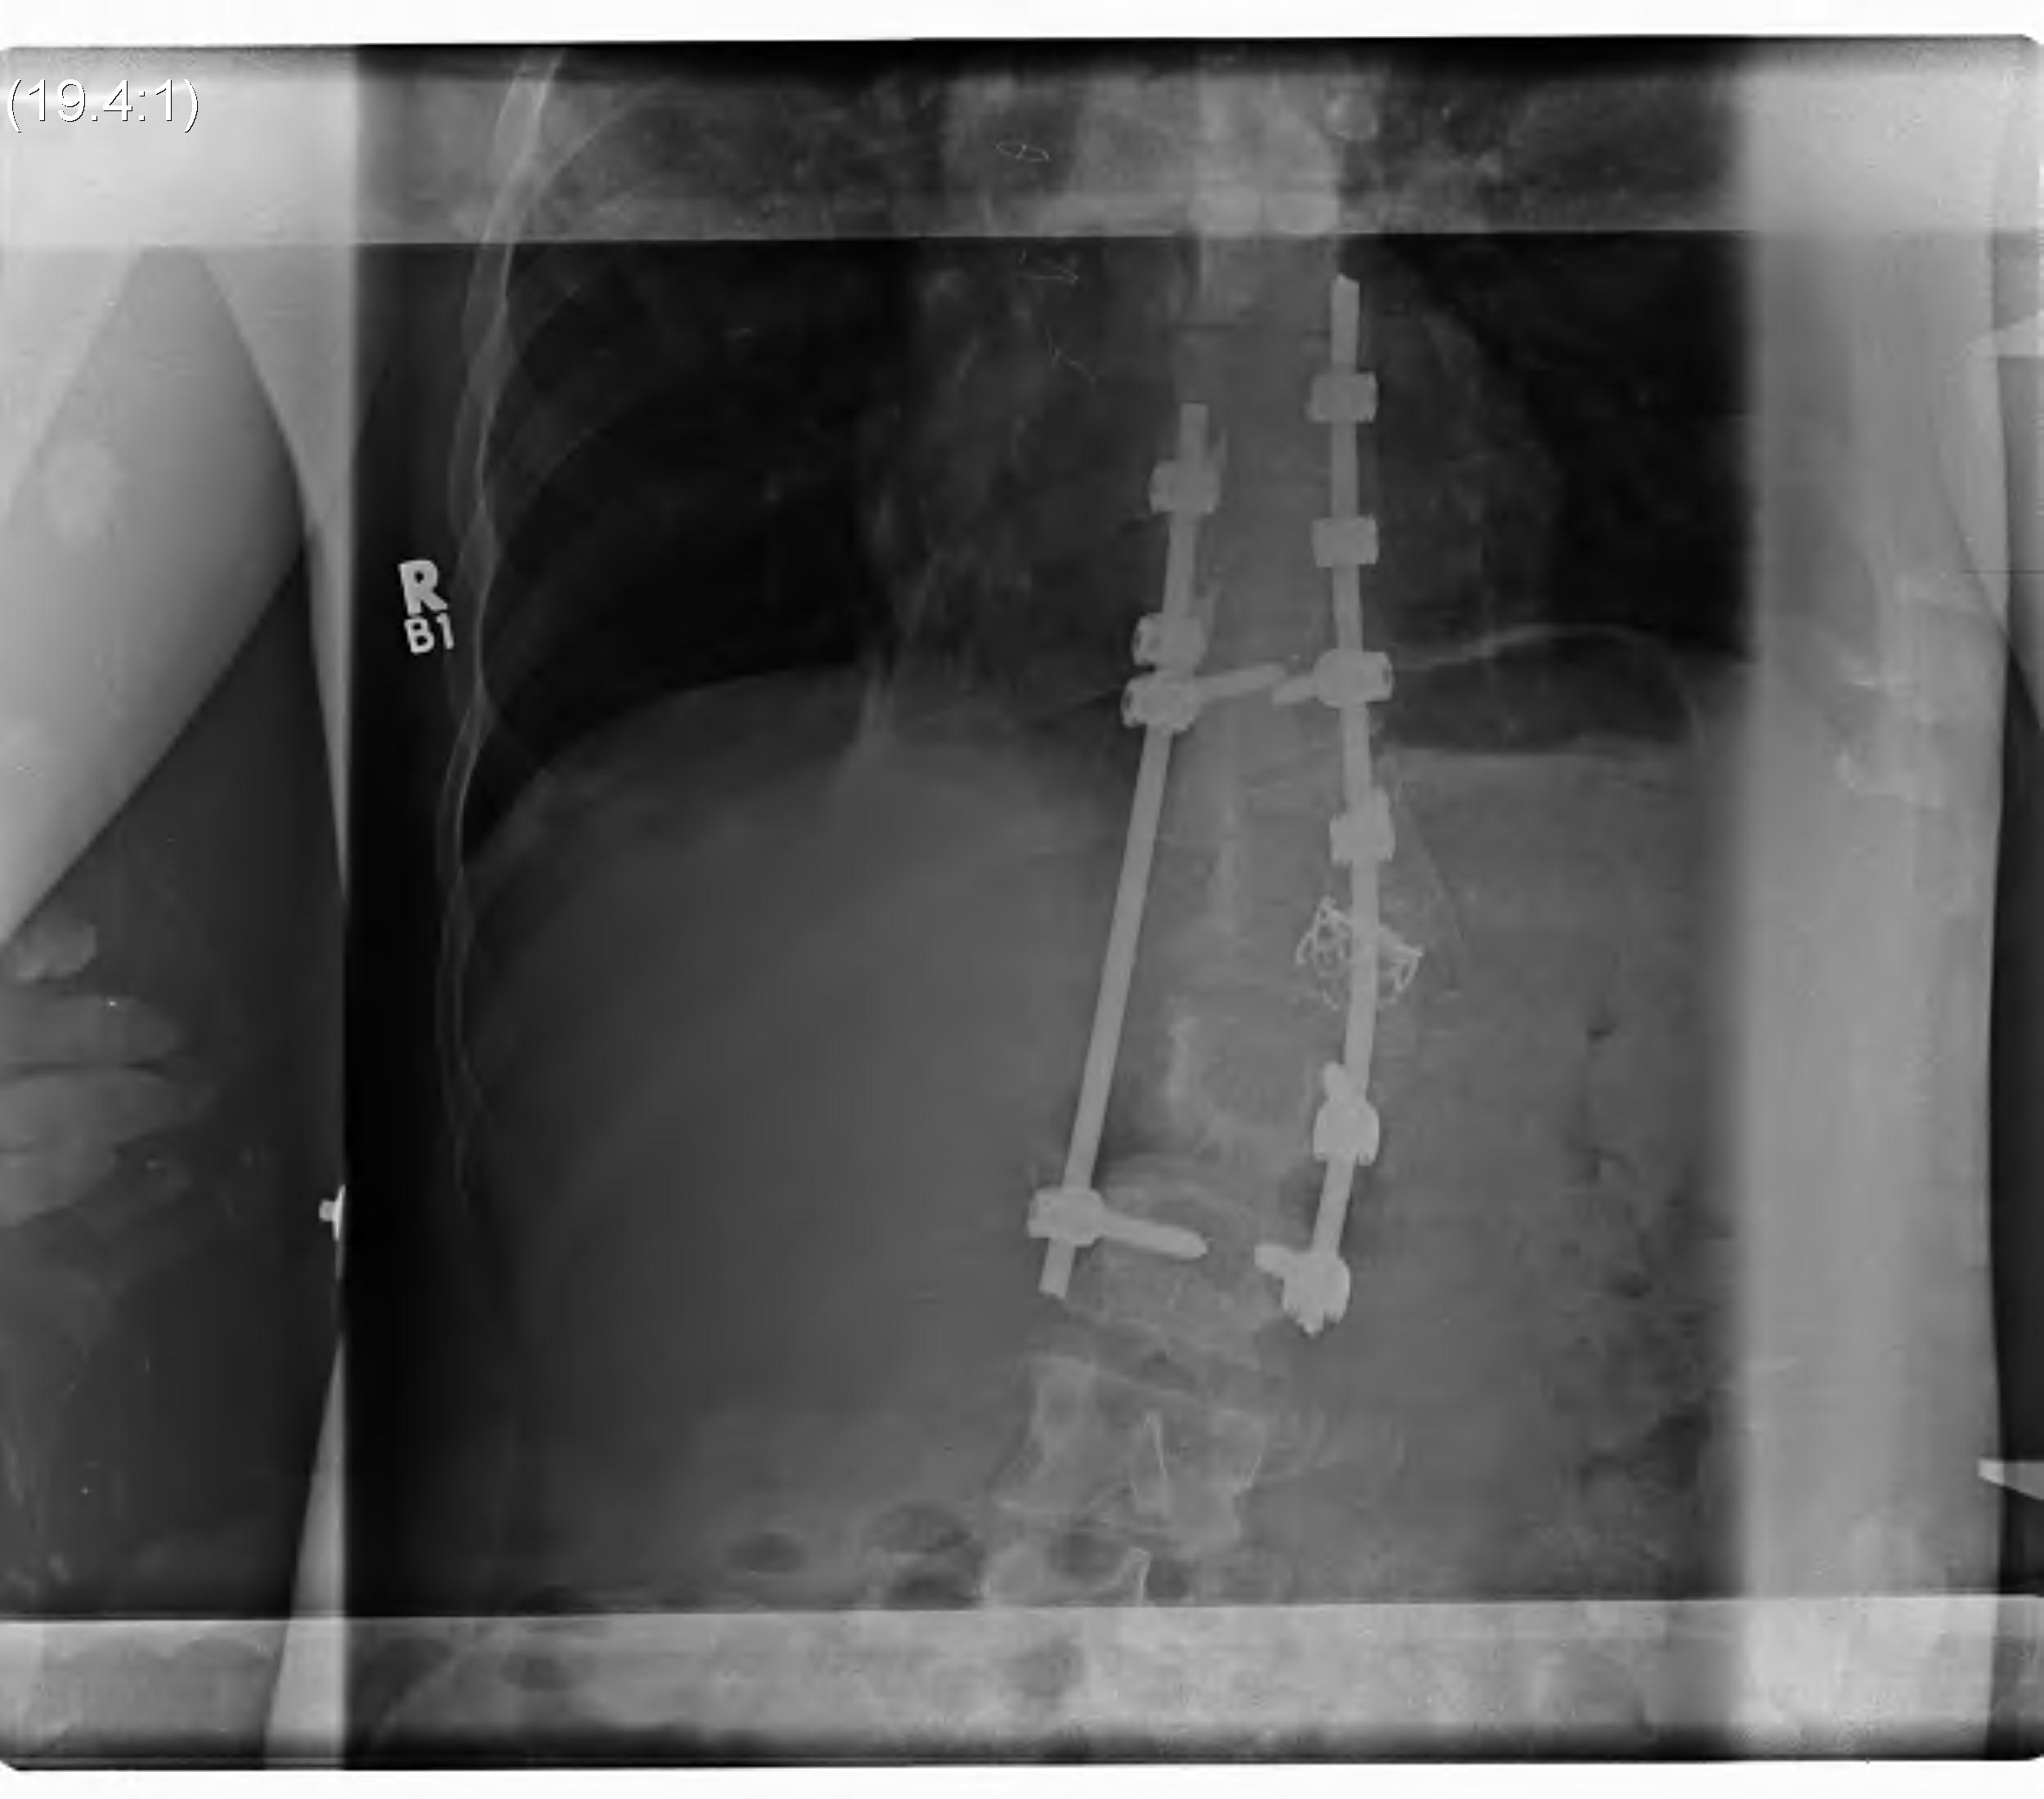

Operative

Type I

Ideal treatment is early detection & early posterior fusion

A. < 5 years & curve < 50o

- posterior spinal fusion

B. > 5 years and > 500

- anterior and posterior fusion